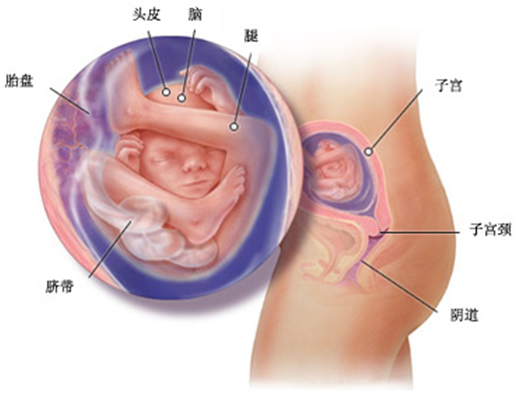

胎儿现在大约有 225 克,身体比上个月长了两倍。在孕中期做 B 超时,你可以根据 B 超图画出胎儿的大致模样,当与你丈夫一起去做这项检查时,他可以看到胎儿在踢腿、屈身、伸腰、滚动以及吸吮他(她)的大拇指。

现在医生可以清晰地分辨胎儿性别了,但是由于目前部分父母存在性别歧视,医生一般不会告诉你胎儿的性别。

健康地进入孕中期你一定很欣慰吧,现在胎儿的身长已经达到 16.5 厘米,体重达到 250 克。胎儿的感觉器官进入成长的关键时期,大脑开始划分专门的区域进行嗅觉、味觉、听觉、视觉以及触觉的发育。如果胎儿是个女孩,她的卵巢里现在大约有 6 百万个卵,在她出生时卵的数目将逐渐减少到 1 百万。

你的腹部已经逐步适应了不断增大的子宫,现在是丈夫帮助你每周测量宫高的时候了。宫高是指从下腹耻骨联合的上沿至子宫底间的长度,从现在开始,每周的宫高都应增加 1 厘米,如果持续 2 周没有变化,就应请医生做检查。孕晚期胎头进入骨盆后,宫高的上升速度会减慢。从孕 20 周起,胎儿的视网膜就形成了,开始对光线有感应,这时你可以用手电照射腹部进行胎教,他(她)对强光的反应会很大。